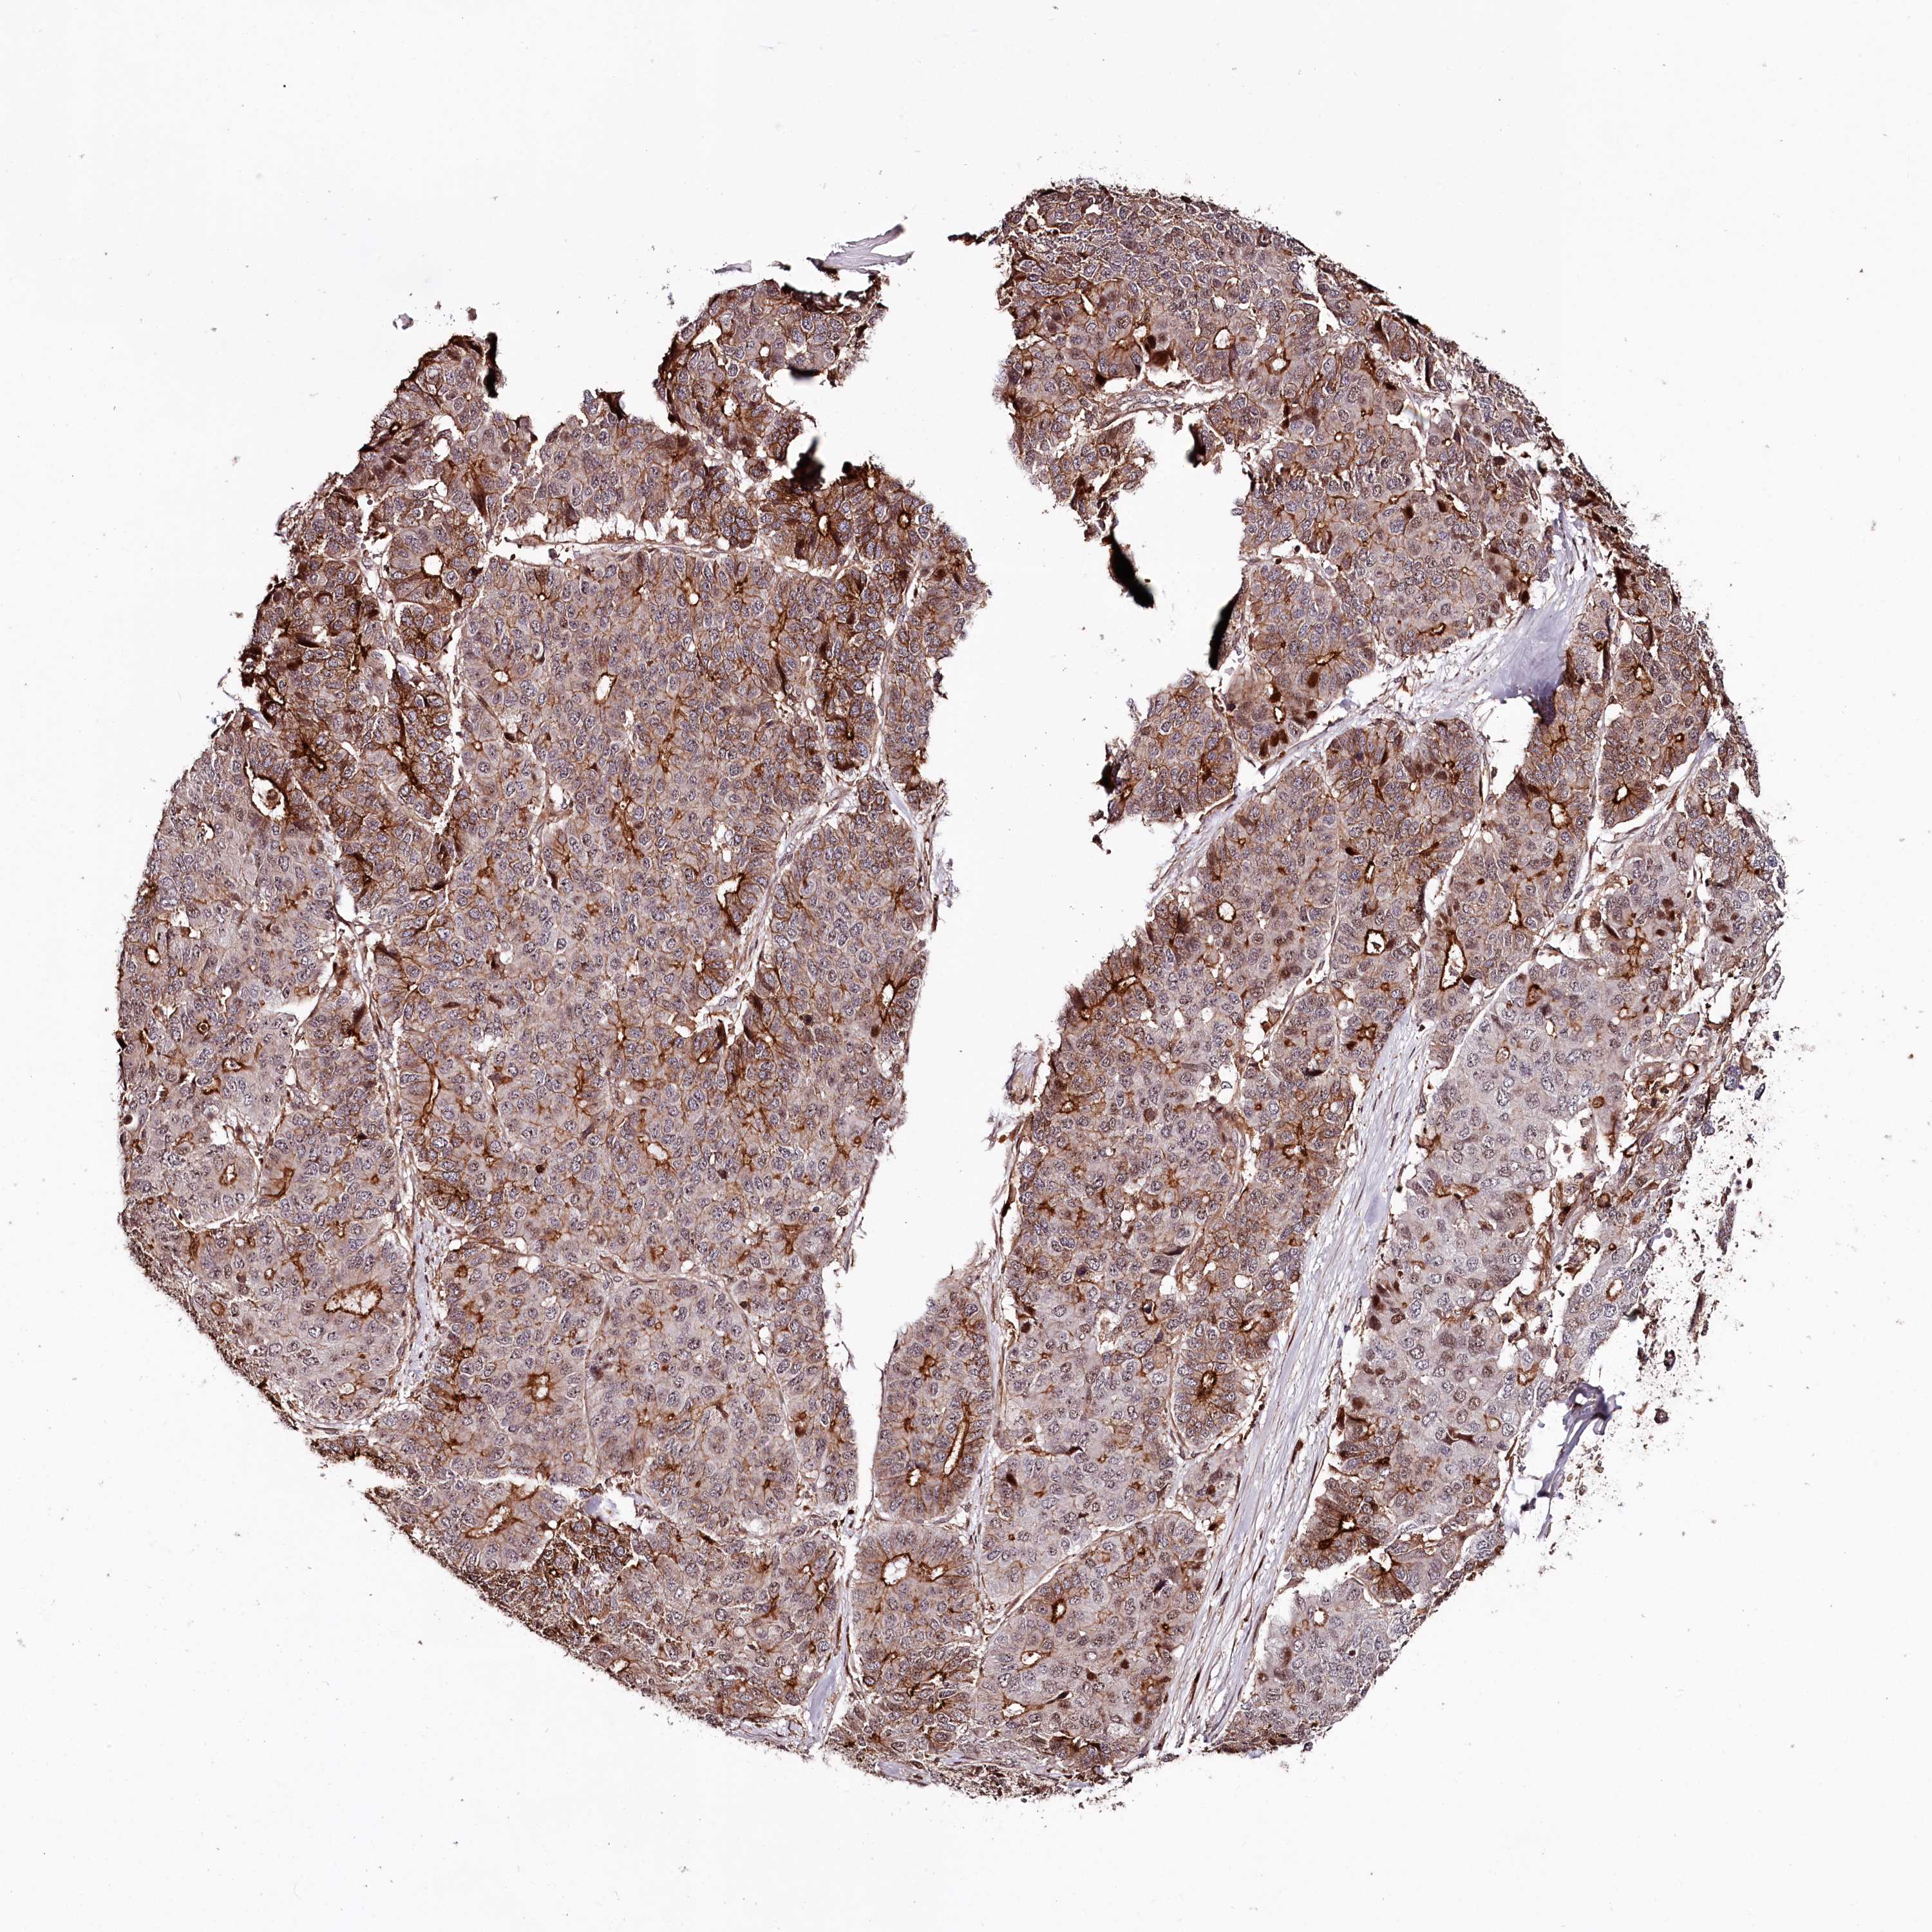

PANCREATIC CANCER - Protein expressioni

A mouse-over function shows sample information and annotation data. Click on an image to view it in a full screen mode. Samples can be filtered based on level of antibody staining by selecting one or several of the following categories: high, medium, low and not detected. The assay and annotation is described here.

Note that samples used for immunohistochemistry by the Human Protein Atlas do not correspond to samples in the TCGA dataset.

Antibody stainingi

Antibody staining in the annotated cell types in the current human tissue is reported as not detected, low, medium, or high, based on conventional immunohistochemistry profiling in selected tissues. This score is based on the combination of the staining intensity and fraction of stained cells.

Each image is clickable and will lead to virtual microscopy that enables deeper exploration of all samples and also displays staining intensity scores, fraction scores and subcellular localization as well as patient and tissue information for each sample.

Antibody HPA038061

Staining

High

Medium

Low

Not detected

Intensity

Strong

Moderate

Weak

Negative

Quantity

>75%

75%-25%

<25%

None

Location

Nuclear

Cytoplasmic/membranous

Cytoplasmic/membranous,nuclear

Adenocarcinoma, NOS